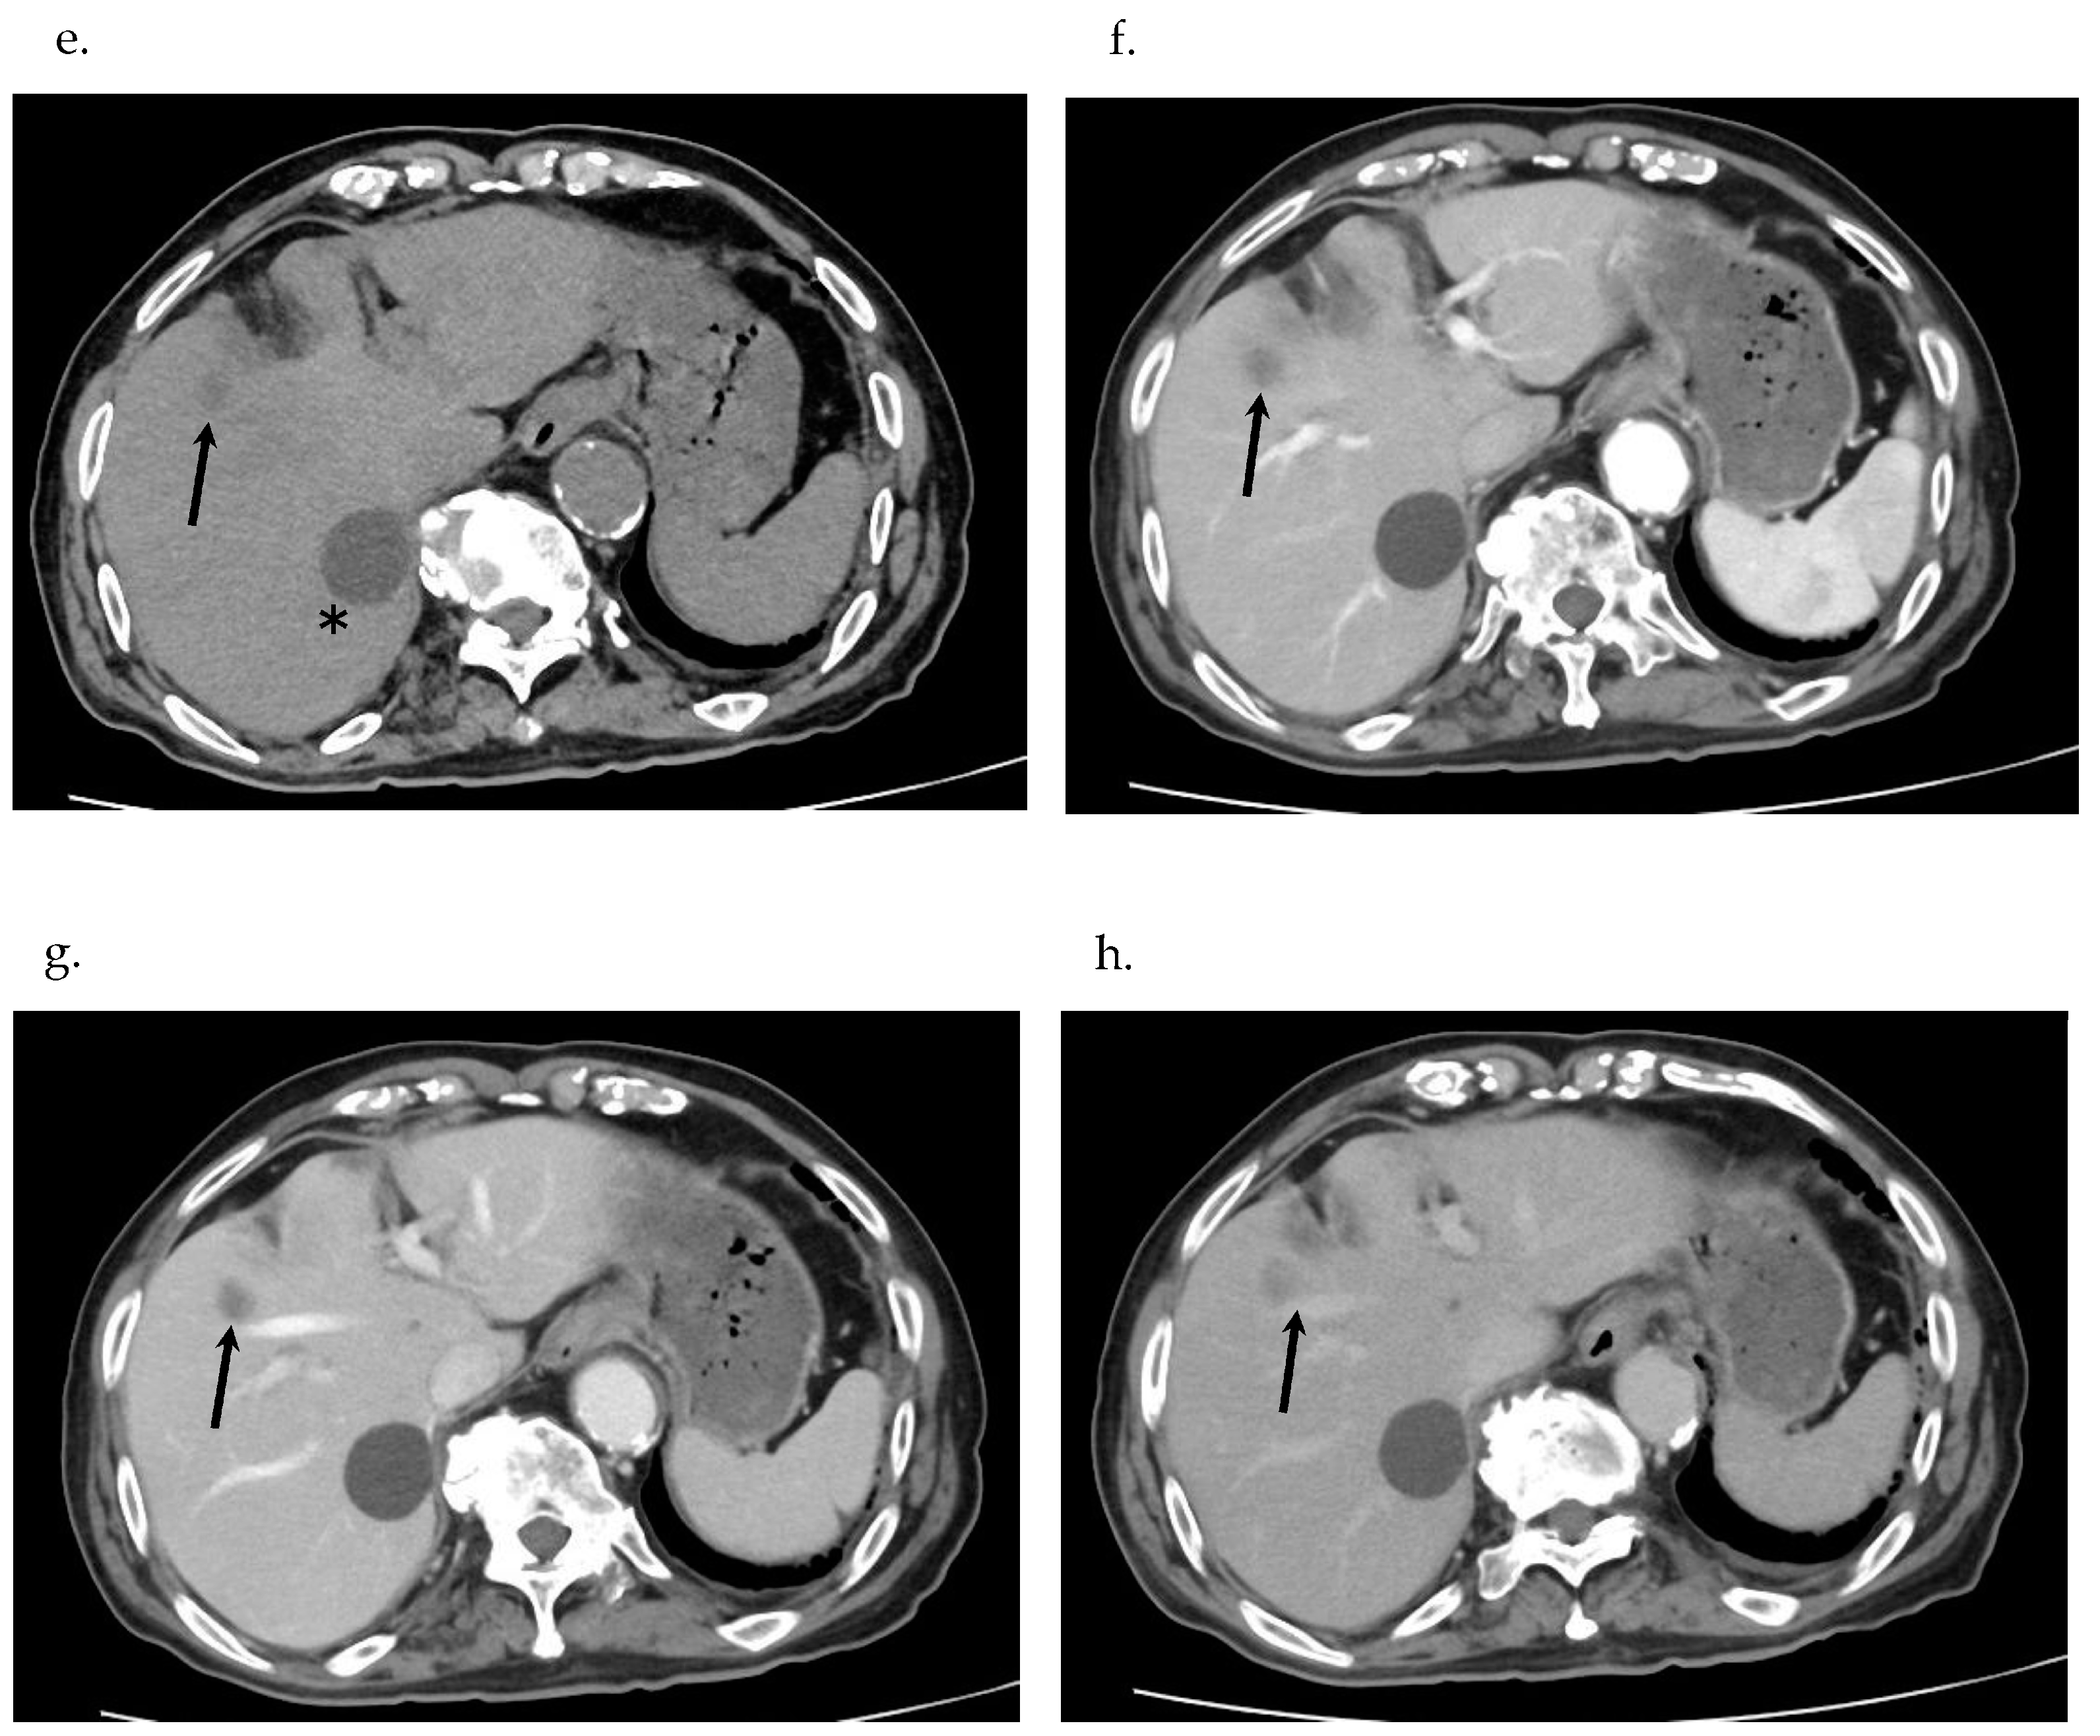

2.6. Imaging Examinations

- Based on pathological findings, the liver tumor was diagnosed as poorly differentiated SCC. Clinically, no primary focus suggesting a metastatic liver tumor in other organs was in evidence; based on GIF, CF, CT and DWIBS, the tumor was finally diagnosed as primary SCC of the liver. Also clinically, the nodule in S6 was a primary SCC lesion and multiple nodules located in S5 and S8 were interpreted as the result of intrahepatic spread from one of the primary SCCs of the liver.

7.3. Imaging